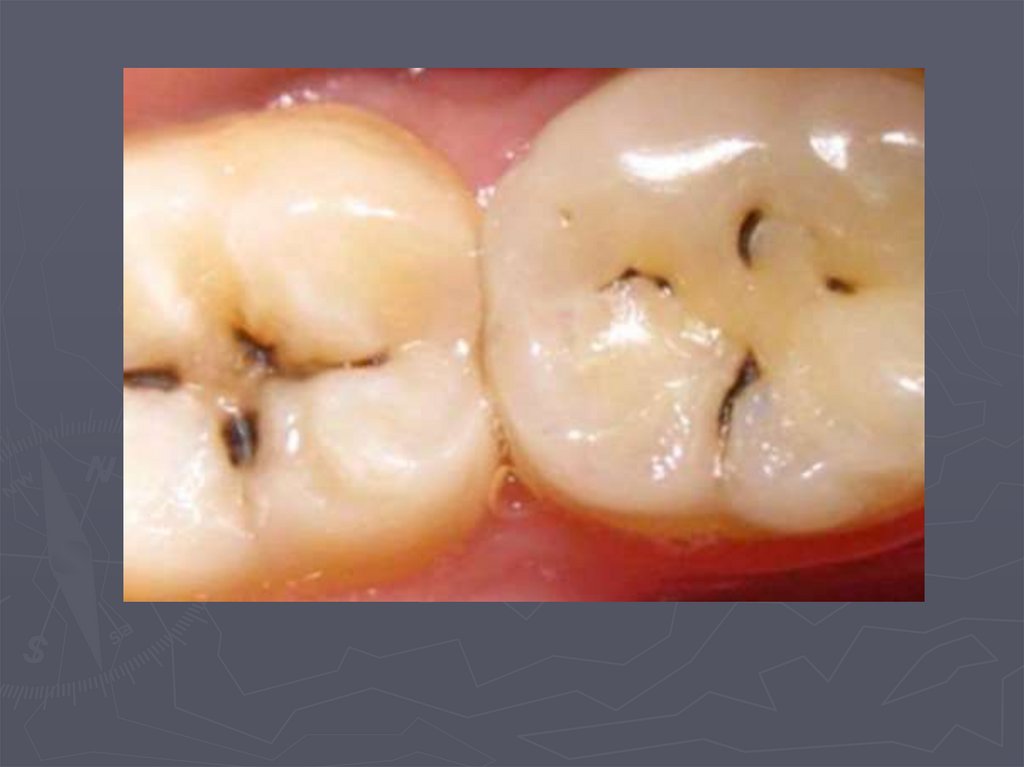

37. КЛИНИЧЕСКАЯ КАРТИНА СРЕДНЕГО КАРИЕСА при компенсированной форме:

► отмечается быстропроходящая боль от

химических, термических, иногда от

механических, раздражителей;

► края кариозной полости закругленные, ровные;

► эмаль плотная;

► дентин плотный, пигментированный;

► при зондировании болезненность определяется

по эмалево-дентинному соединению.

38. КЛИНИЧЕСКАЯ КАРТИНА СРЕДНЕГО КАРИЕСА при декомпенсированной форме:

► при локализации кариозной полости в фиссурах

определяется небольшое входное отверстие;

► при раскрытии обнаруживается кариозная

полость с податливым дентином;

► края кариозной полости нависают;

► эмаль тонкая, хрупкая;

► дентин светлый, влажный, размягченный, легко

удаляется экскаватором;

► зондирование болезненно по

эмалево-дентинному соединению.